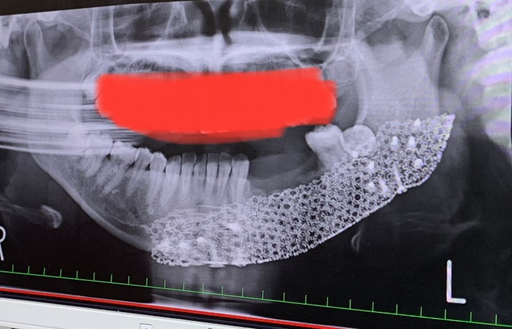

翌日、大病院を受診し、レントゲンを撮影した結果、正式に「エナメル上皮腫」であると告げられた。

医師との相談により、じゃすみんさんは左下顎を切除することに。切除した箇所にはチタンのメッシュプレートを埋め、左右の腰の骨を移植。

「手術は5時間。首の下に15cmほど、左右の腰には5cmほどの手術痕が残り、顎骨の切除によって、左下の中間から奥歯を3本失いました」